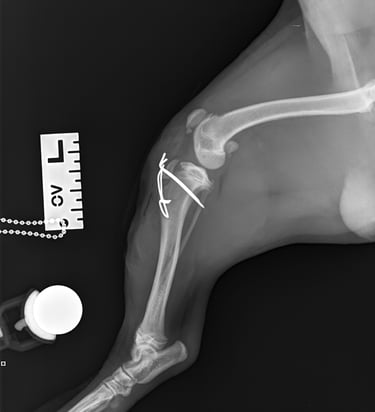

Lateral radiographs revealed a complete avulsion of the left tibial crest (Fig. 1), along with a mild lesion at the distal pole of the patella. For comparison, a lateral view of the right limb is included, demonstrating a normal appearance of the tibial crest growth plate (Fig. 2).

Fig. 2